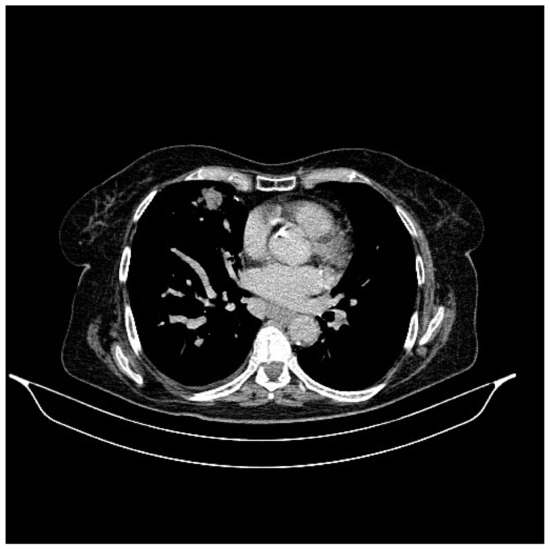

2. Case Presentation